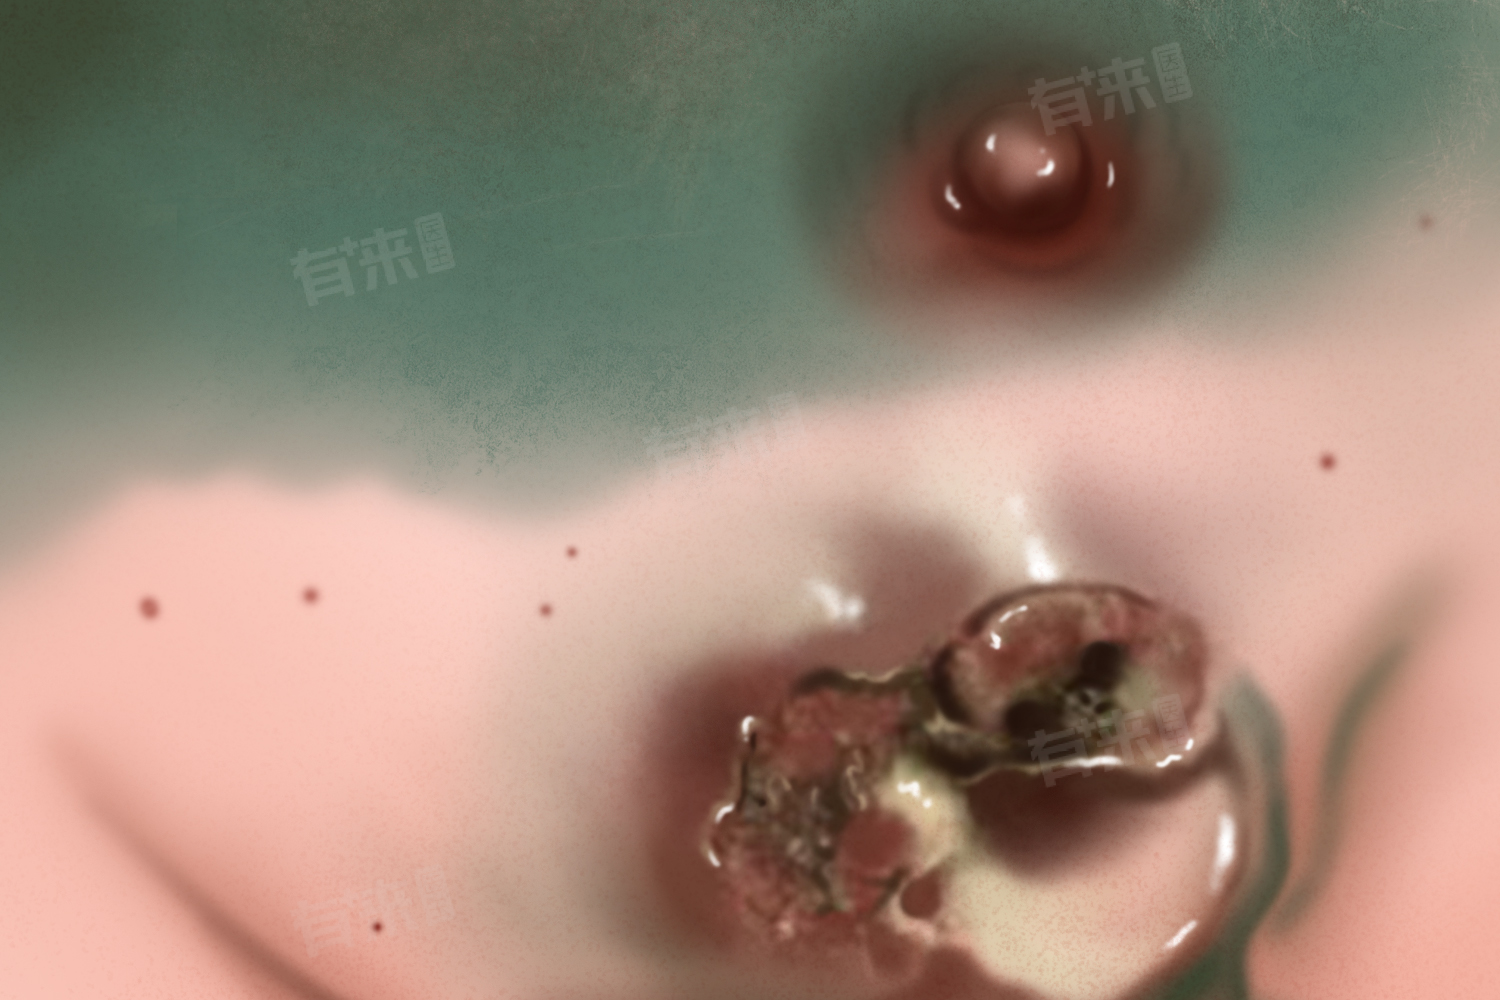

乳腺肿瘤破了流血水是一个需要及时处理的紧急情况,患者应立即就医并在医生指导下进行综合治疗,包括一般治疗、药物治疗、手术治疗、放疗与化疗等。同时,患者还应注意保持良好的生活习惯和心态,积极配合医生的治疗计划以促进病情恢复。